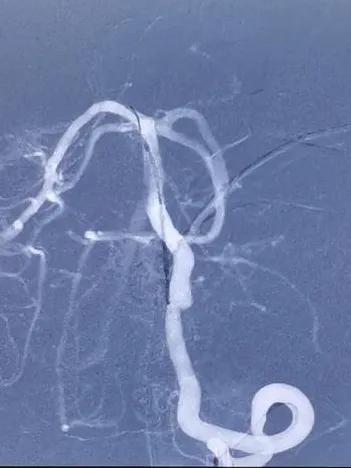

支架置入过程

术后图像

造影显示病变部位造影剂滞留。载瘤动脉通畅,脊髓前动脉通畅。后分别行左右颈内动脉及右侧椎动脉正侧位造影,未见明显血管异常。